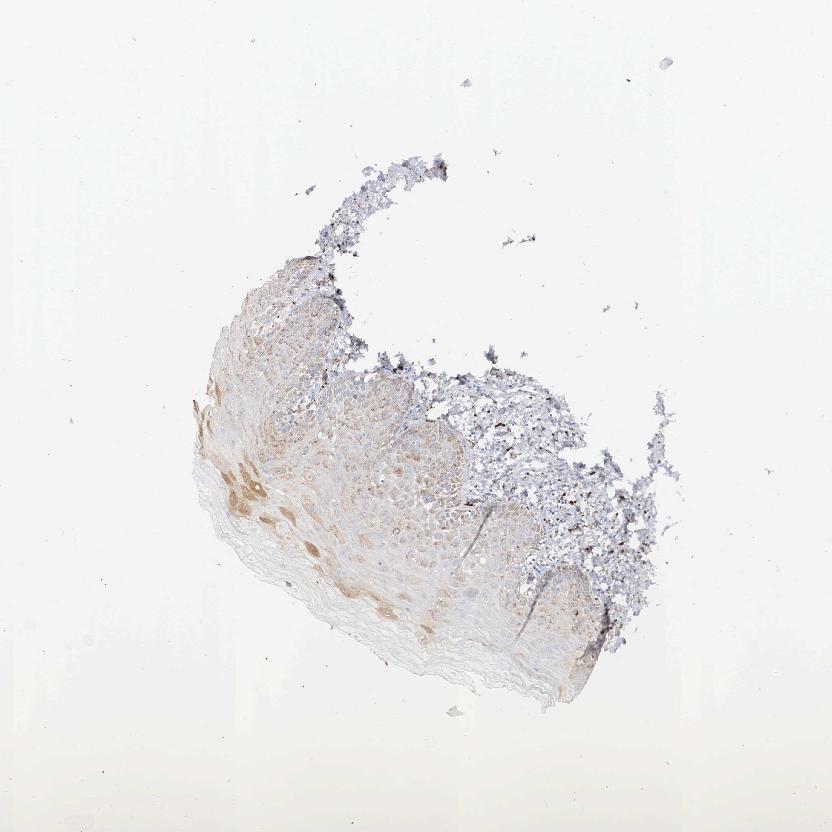

TISSUE PRIMARY DATA ORAL MUCOSA Show tissue menu

ORAL MUCOSA - Antibody stainingi

Antibody staining in the annotated cell types in the current human tissue is reported as not detected, low, medium, or high, based on conventional immunohistochemistry profiling in selected tissues. This score is based on the combination of the staining intensity and fraction of stained cells.

Each image is clickable and will lead to virtual microscopy that enables deeper exploration of all samples and also displays staining intensity scores, fraction scores and subcellular localization as well as patient and tissue information for each sample.

Antibody HPA000410Antibody HPA000554

Squamous epithelial cells MediumNot detected